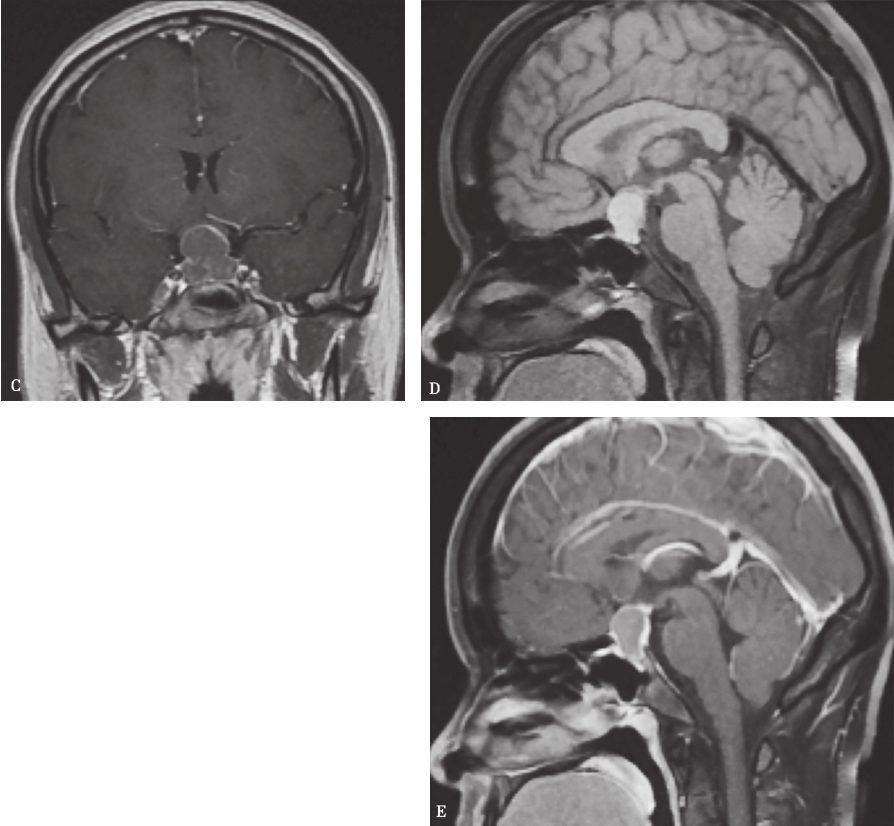

图1Rathke囊肿的MRI表现

鞍区及鞍上囊性占位,以中线大致对称分布,T1及T2WI 呈高信号,壁菲薄,囊内见T2WI 低信号结节影,增强后呈薄壁环形强化,不完整,囊内结节无明显强化;A.冠状位T1WI;B.冠状位T2WI;C.增强冠状位T1WI;D.矢状位T1WI;E.增强矢状位T1WI